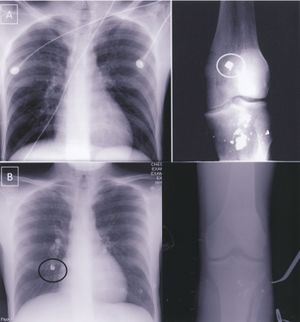

(B)Post operative CXR and plain films of the right knee demonstrate embolization of knee fragment to right lower lobe (black circle) when compared to preoperative films (A) [2]